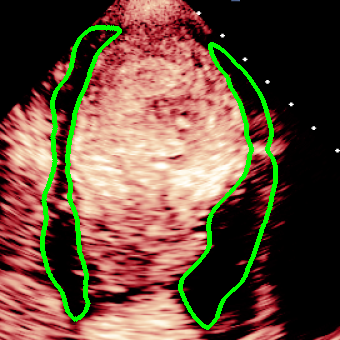

For variations caused by low quality images such as those of low resolution or significant artifacts, however, the unique ground truth may not be available. Take the myocardial segmentation task of Myocardial Contrast Echocardiography (MCE) as an example. An inter-observer experiment was conducted among five experienced cardiologists, and Fig. 1(a)(b) visualize the annotations of two images from three of these cardiologists. It can be seen that the labels by different cardiologists vary significantly, especially in locations where the intensity information of myocardium is very similar to the background. Table 1 shows the average Dice of the annotation of each cardiologist, using one of the others’ as the ground truth, over 180 images. We can observe that none of the Dice is above 0.9, some even under 0.8, confirming significant variations among the annotations. In this case, as the variations are caused by the image quality, even these cardiologists cannot tell which annotation is better than others, and a majority vote for ground truth would not make sense sometimes as can be seen in Fig. 1(c)(d). For this reason, we cannot obtain a unique ground truth in the evaluation process and the traditional metrics such as Dice and IoU cannot be used.